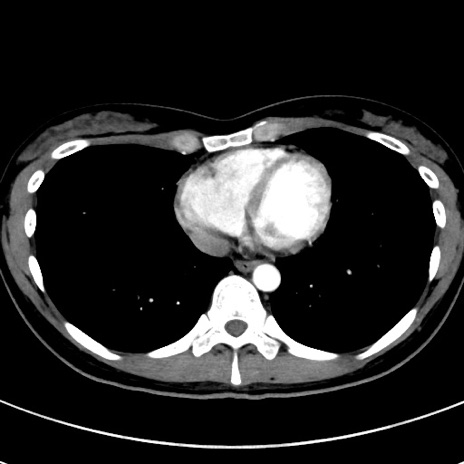

症例17(横断像)

【症例】20歳代女性

【主訴】嘔吐、下腹部痛

【現病歴】昨日夕食後に嘔吐し下腹部痛が出現。本日になっても嘔吐持続し改善しないため来院。

【身体所見】意識清明、BT 37.2℃、BP 108/67mmHg、腹部:平坦、やや硬、下腹部正中から右にかけて圧痛あり、反跳痛軽度あり、tapping pain(+)。

【データ】WBC 13600、CRP 14.94